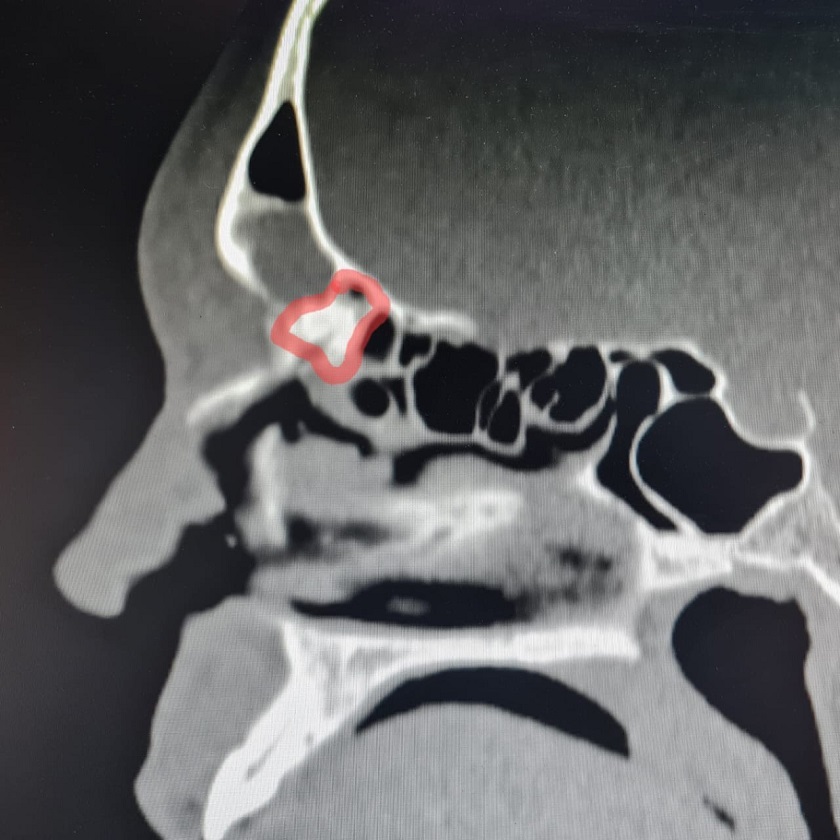

Фото: Елена Разумеева/Вконтакте. На снимке пазуха с блокированными путями оттока.